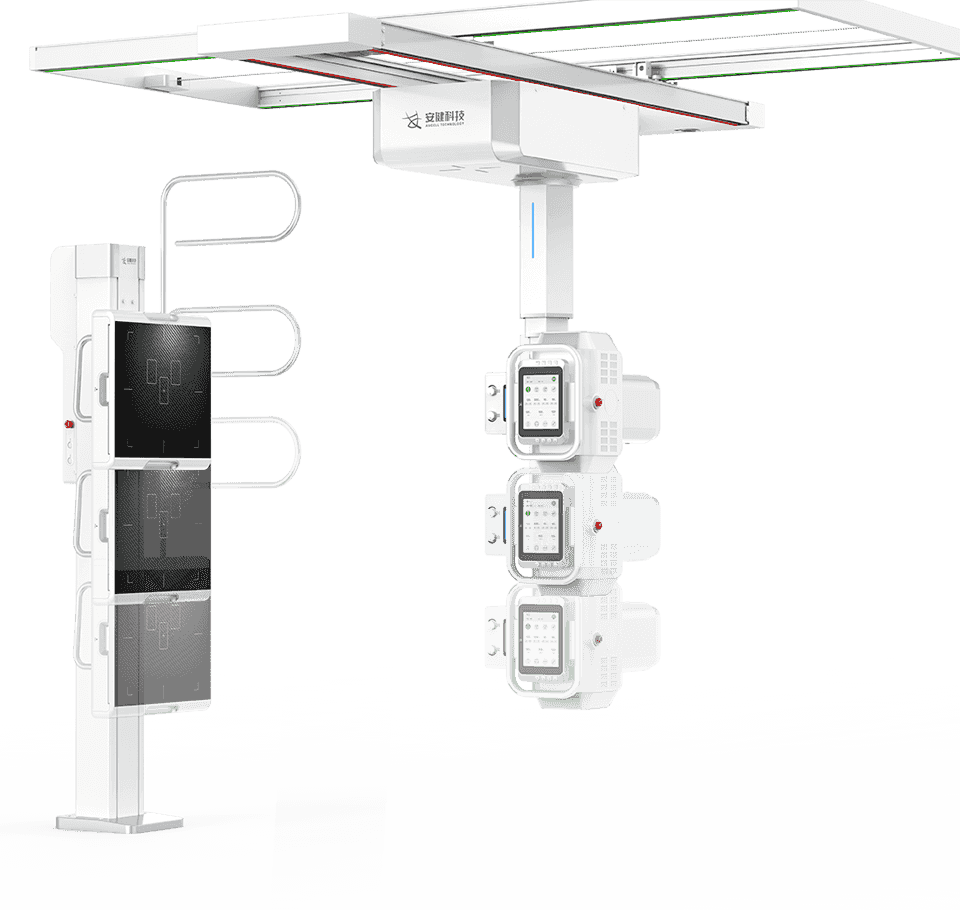

4DК®ЦбБЄ¶ЇФЛ¶ЇПµНі

¶а№¦ДЬРьµхКЅ»ъРµФЛ¶ЇЈ¬И«ЖЅєвОИ¶ЁРФЙијЖЈ¬4DК®ЦбБЄ¶ЇјјКхЈ¬»ъјЬФЛ¶ЇЧФИзЖЅОИЈ¬

ЕдєПµз¶ЇЙэЅµґІј°¶а№¦ДЬБўКЅЙгУ°јЬЈ¬ЗбЛЙВъЧгБЩґІИ«МеО»ЙгУ°РиЗуЎЈ

¶ЇѕІЛ«°еЧФУЙЗР»»

¶ЇМ¬ЖЅ°е+ѕІМ¬ЖЅ°еЛ«°еЕдЦГЈ¬їЙКµПЦєБГлј¶СЎ°еЗР»»ЎЈ

ЕдєПКЦЧФТ»МеРьµхКЅ»ъРµФЛ¶ЇПµНіЈ¬¶аМеО»ЕДЙгЧЄ»»ЗбЛЙЧФИзЈ¬ґу·щМбЙэБЩґІјмІйР§ВК -

µНМеО»Бй»оЕДЙг

МЅІвЖчєНЗт№ЬїЙЅµЦБЅфМщµШГжЈ¬НкіЙПВЦ«¶аЅЗ¶ИЙгУ°Ј¬

јхЙЩІЎИЛТЖ¶ЇЈ¬Н¬К±±гУЪ¶щНЇБўО»ЎўЛДЦ«ЕДЖ¬ЎЈ -